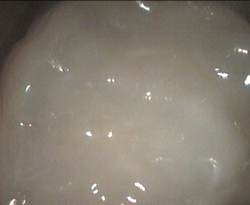

Soft teeth re-surfaced